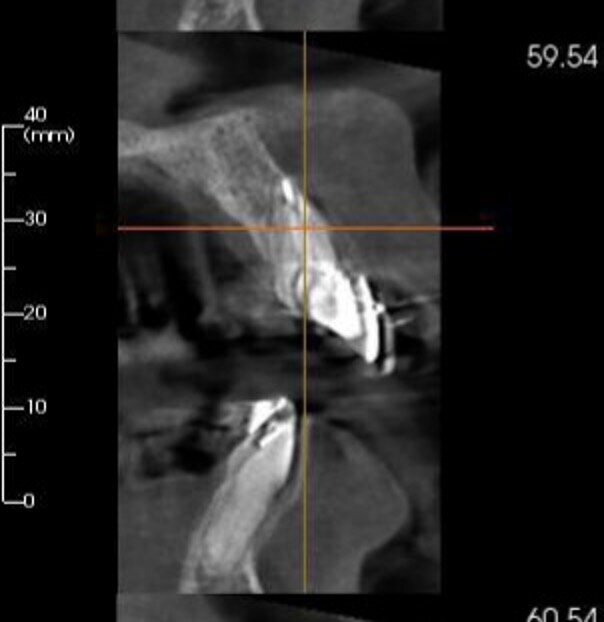

A 37-year-old female patient presented to our practice with advanced mobility of tooth #11. Intra-oral examination found advanced mobility and slight pain on vertical and horizontal percussion. The CBCT scan showed root resorption, making the tooth unrestorable, and an unfavourable root–crown ratio (Fig. 12a). Extraction with immediate implant placement was planned, and a provisional restoration was planned for tooth #11, as was a crown for tooth #12 and veneers for teeth #21 and 22.

Figs. 12a–f: Pre-op CBCT scan showing the resorbed root of tooth #11 (a). Caption (b). Post-op CBCT scan showing the position of the implant in the extraction site (c). Caption (d). A surgical guide was manufactured to help place the implant in the optimum position with respect to the soft and hard tissue (e). Provisional screw-retained crown placed for six months to serve as a guide for soft- and hard-tissue healing (f).

Atraumatic tooth extraction of tooth #11 was performed, debris was removed from the extraction socket and the implant was placed (Fig. 12e). The screw-retained provisional restoration was prepared in imitation of the shape and contour of the socket and a xenograft bone substitute material (Geistlich Bio-Oss) was placed to fill the gap in the dual zone (Fig. 13). A radiograph was taken, and it showed the ideal positioning of the implant (Fig. 12c). The provisional restoration was then placed (Fig. 12f).